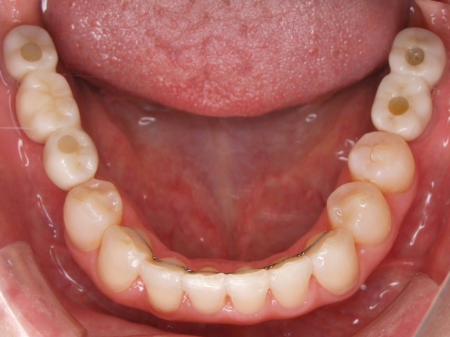

拝見したところ、歯と歯が並ぶ土台の骨「歯槽基底」の大きさの不調和により歯並びがガタガタになる「叢生(そうせい)」が全体的に生じており、また上下の前歯の重なりが深いため下の歯が見えない「過蓋咬合(かがいこうごう)」も認められました。

下の奥歯5本(右第2小臼歯/5番、左右第1大臼歯/6番、左右第2大臼歯/7番)が欠損したまま長く放置されていたことが原因で、噛み合う歯がなかった左上の奥歯(第1大臼歯)は本来の位置より下に伸びる「挺出(ていしゅつ)」が起き、左下の歯2本(第1小臼歯/4番、第2小臼歯)も内側に倒れたことで、下前歯の叢生が悪化したと考えられます。

さらに左上の歯(第1小臼歯)の欠損部位は両隣の歯2本(犬歯/3番、第2小臼歯)を土台に人工歯を橋渡しにする被せ物「ブリッジ」が装着されており、お口を開けたときに銀歯が目立つことに加えて、歯の色が全体的に黄ばんでいるため見た目が良くない状態でした。